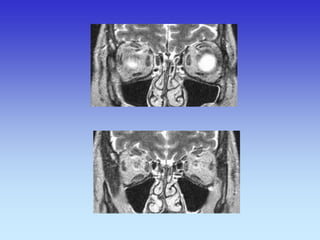

CT- SINUSA KORONARNI SLOJ

1.Maksilarni sinus

2.Septum nasi

3.Orbita

1

2

3

1.Sfenoidni sinus

2.Tvrdo nepce

3.Prednji klinoid